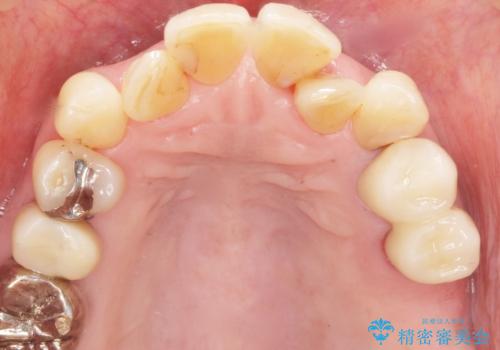

奥歯の違和感 再根管治療 40代女性

- 奥歯の違和感を主訴に来院された患者様です。

精査したところ、左上の大臼歯2本(左上67)が欠損しており、左上の小臼歯2本(左上45)は根が短く動揺があり根尖病変を認めました。

「大臼歯は入れ歯かインプラントを検討しているがまだやりたくないため、小臼歯のみを治療してほしい」との患者様のご希望により、

相談を重ねた上で小臼歯2本の再根管治療と連結補綴を行いました。

大臼歯がないため小臼歯に負担がかかりやすいことによるリスクを説明し、ご理解頂いた上で治療を行いました。

気にされていた歯の動揺や違和感がなくなり、喜んで頂けました。

モチベーションがあがり、大臼歯欠損部位の治療に関しても前向きに検討して下さるとの事でした。

クラウンの種類:オールセラミッククラウン スタンダード